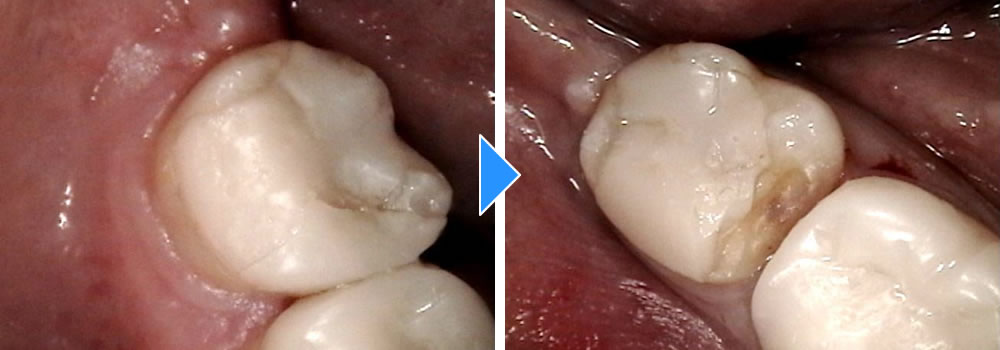

再発した虫歯をセラミックインレーで治療した症例

再発した虫歯をセラミックインレーで治療した症例 こちらの患者さまは、定期検診希望で3年ぶりに来院されました。 左下5番目の歯の詰め物が劣化し、虫歯が確認できたため、治療をすることになりました。 カウンセラーと詰め物の種類 […]